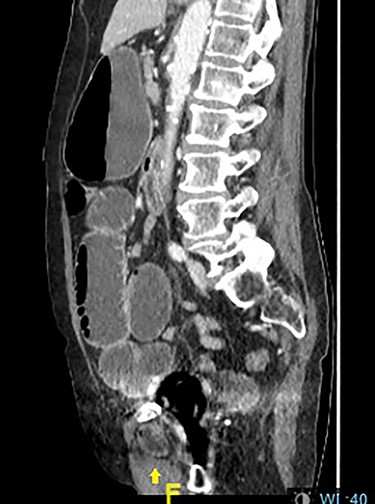

On initial presentation, her blood results were as follows: white cell count (WCC) 14.8 × 109 cells/l (RR 4.3–11.2 cells/l), neutrophils 12.3 × 109 cells/l (RR 2.1–7.4 cells/l) and C-reactive protein (CRP) 1.9 mg/l (RR 0–5 mg/l). Imaging performed included an abdominal film, which showed nonspecific bowel gas pattern (Fig. 1). The patient was managed conservatively and discharged home. She represented 2 days later with worsening symptoms and blood results of WCC 20.1, neutrophils 18.4 and CRP 6. She was admitted under the surgical team and a thoracic and abdominal CT scan was done (Figs 2–4). It was initially reported as significant dilated small bowel loops in keeping with small bowel obstruction due to a femoral hernia. However, the scan was revisited by the surgical team in more detail as the images appeared to represent an obturator hernia. Upon further discussion, these findings were corroborated by the radiologist and a strangulated left obturator hernia was identified.

Distended stomach and dilated bowel loops with an obturator hernia (pointed by the arrow), as shown in the sagittal section.